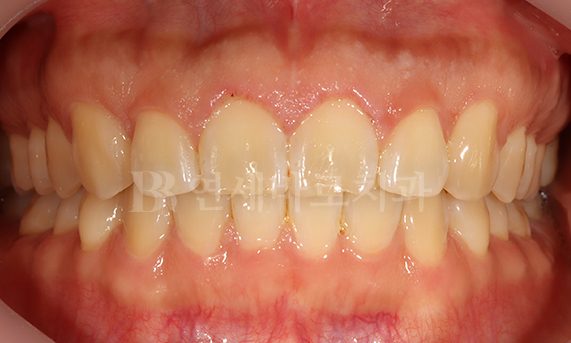

덧니 교정 CASE

연세바로치과는 치료법을 준수합니다. 로그인 하시면 Before를 보실 수 있습니다. LOGIN